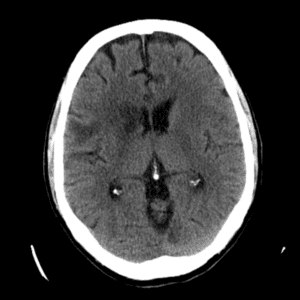

Case #14

CNS toxoplasmosis